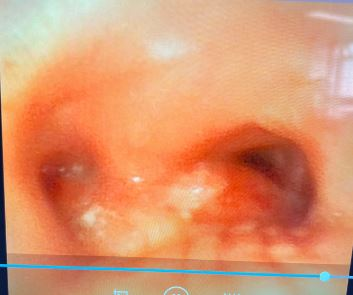

插入硬镜置入导丝引导支架放置

2026年3月31日下午3时,在费卫东等麻醉团队密切配合下,先对患者进行全麻、肌松,呼吸介入专家俞小卫带领下,黄燕华、陈意、刘志光主任紧密配合,利用STOZE 成像系统引导,成功插入硬质气管镜鞘管,在高频通气保驾下,置入导丝,沿导丝插Y形支架到位后逐步释放支架,支架到位,最后采用球囊对支架进行扩张塑形,支架贴壁良好。